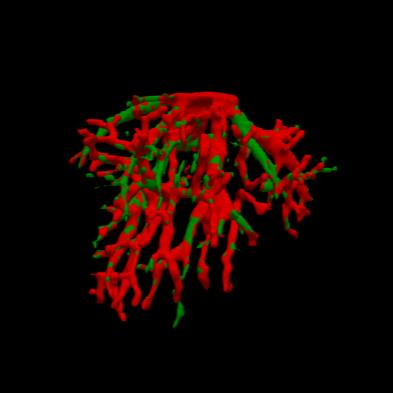

Manually segmenting the hepatic vessels from Computer Tomography (CT) is far more expertise-demanding and laborious than other structures due to the low-contrast and complex morphology of vessels, resulting in the extreme lack of high-quality labeled data. Without sufficient high-quality annotations, the usual data-driven learning-based approaches struggle with deficient training. On the other hand, directly introducing additional data with low-quality annotations may confuse the network, leading to undesirable performance degradation. To address this issue, we propose a novel mean-teacher-assisted confident learning framework to robustly exploit the noisy labeled data for the challenging hepatic vessel segmentation task. Specifically, with the adapted confident learning assisted by a third party, i.e., the weight-averaged teacher model, the noisy labels in the additional low-quality dataset can be transformed from "encumbrance" to "treasure" via progressive pixel-wise soft-correction, thus providing productive guidance. Extensive experiments using two public datasets demonstrate the superiority of the proposed framework as well as the effectiveness of each component.

翻译:将来自计算机地形学(CT)的肝脏船只人工分割,由于船只的低调和复杂形态,由于低调和复杂的形态,造成极端缺乏高质量的标签数据,因此比其他结构更需要专门知识和难度大得多。如果没有足够的高质量的说明,通常的数据驱动的基于学习的方法就会与不足的培训斗争。另一方面,直接引进低质量说明的额外数据可能会混淆网络,导致不良的性能退化。为了解决这一问题,我们提议建立一个新的、由教师协助的、有说服力的、有说服力的学习框架,为具有挑战性的肝脏船只分解任务强有力地利用响亮的标签数据。具体地说,在第三方(即加权平均教师模式)的协助下,经过变通的自信学习后,额外低质量数据集中的噪音标签可以从“阻力”转变为“压力”,通过渐进式的像素方法的软校正,从而提供富有成效的指导。使用两个公共数据集进行的广泛实验,显示了拟议框架的优越性以及每个组成部分的效能。